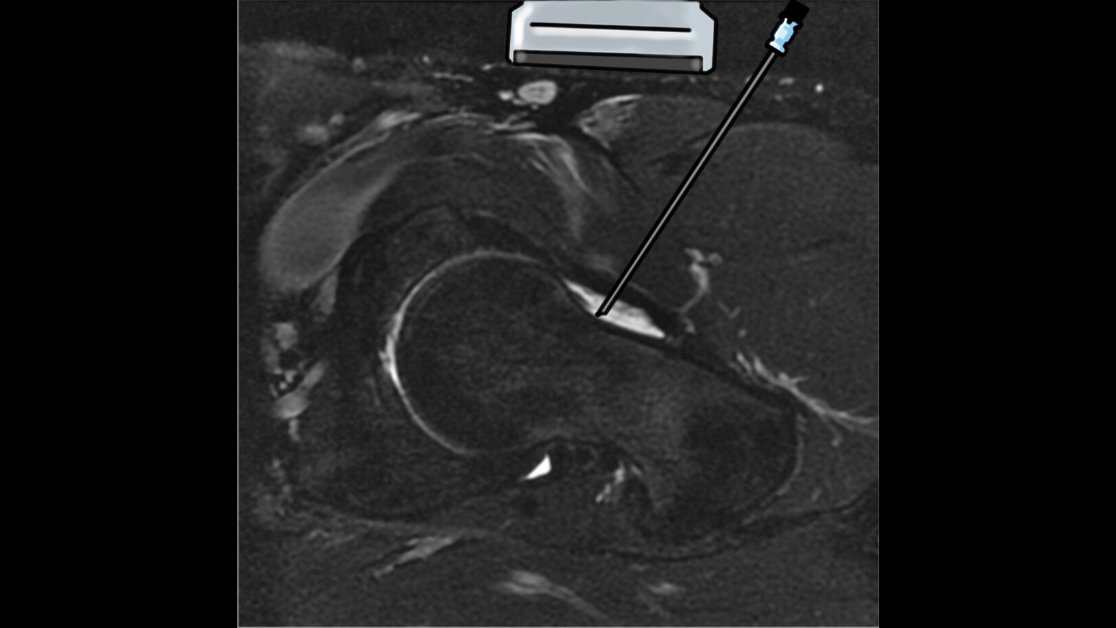

Blaichman et al describe common and advanced US-guided interventions, including percutaneous viscosupplementation, platelet-rich plasma injection, and microwave ablation, that can be performed to treat hip pain. https://bit.ly/35Fz1PY

@UWiscRadiology@UBC_Radiology#MSKRadpic.twitter.com/1RCmuyuf3l